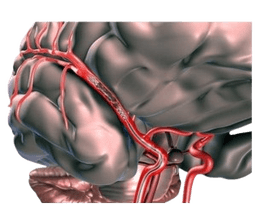

Cerebral of Brain Aneurysm

Cerebral aneurysm, also known as brain aneurysm, is a small and thin spot on the artery in the brain that bulges out and fills with blood. As a result, the bulging aneurysm leads to force or puts pressure on the nerves or brain tissue. This can also result in a burst, spilling blood surrounding tissue, known as hemorrhage. Consequently, a ruptured aneurysm can be a life-threatening condition, such as hemorrhagic stroke, brain damage, coma, or sometimes death.-br However, some cerebral aneurysms do not bleed, and are very small in size or cause other complications. These types of aneurysms are diagnosed while imaging tests for different medical problems. Cerebral aneurysms can take place anywhere in the brain, but most develop in major arteries along the base of the skull.-br Cerebral of brain aneurysms can develop at any age and anywhere in the brain. They are, however, most common in adults between the ages of 30 and 60 years, and are more common in females than males. Additionally, some patients are at high risk due to inherited disorders.